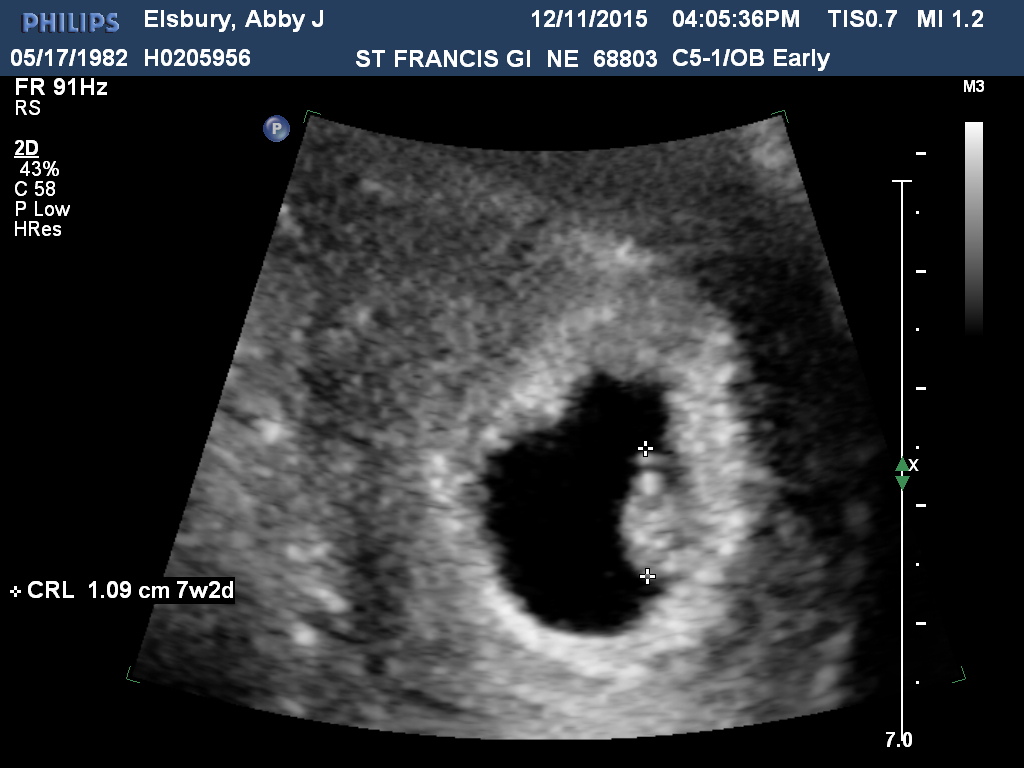

December 11th - 7 weeks 2 days.

I was panicking because of some spotting. I love that my doctor is on the safe side and ordered another ultrasound. Baby grew and the heart beat was stronger. A breath of relief. :)